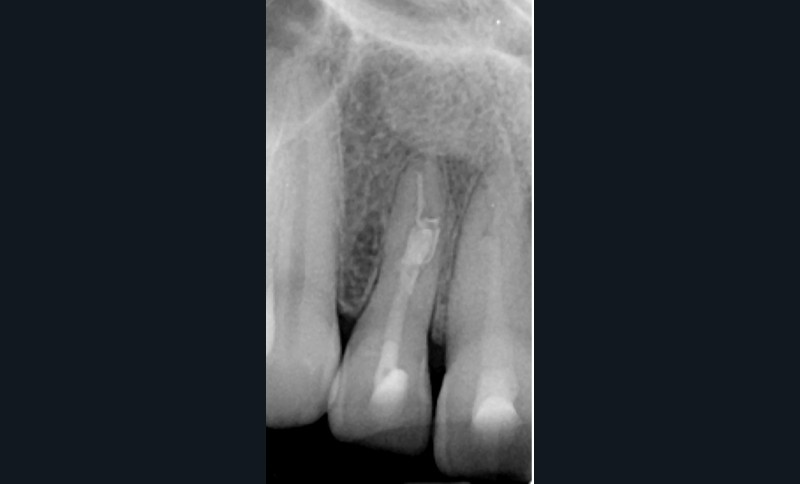

Si l’étude de Peters [18] nous montre que l’instrumentation laisse 35 % du volume canalaire non instrumenté, Ricucci et Siqueira montrent que la préparation physico-chimique n’élimine que partiellement les tissus nécrotiques à l’entrée des canaux latéraux, des isthmes et des ramifications apicales, en laissant des tissus enflammés et infectés, en association avec des lésions apicales [29] (fig. 4 et 5).

Fig. 4 – Coupe d’une racine mésiale de molaire mandibulaire avec deux canaux traités. Coupe à 3 mm de l’apex, coloration Brown et Brenn, technique modifiée par Taylor. Ces images montrent un isthme étroit avec une infection bactérienne, ce qui prouve l’importance de désinfecter et d’inclure l’isthme dans les traitements conventionnels et dans les rétropréparations apicales en chirurgie endodontique.